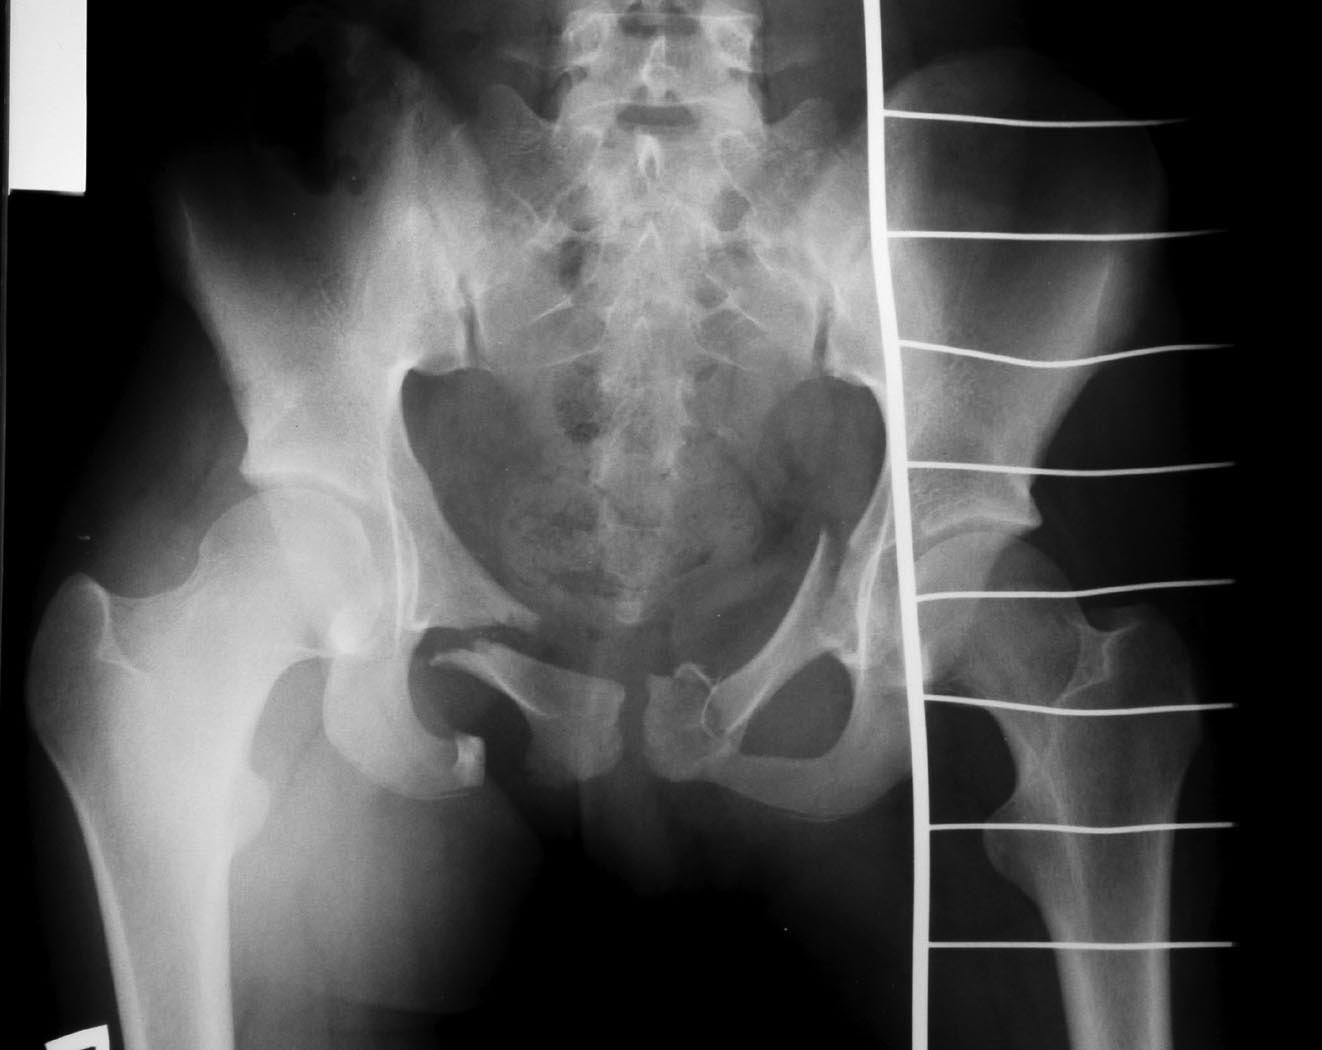

[Ortho] Перелом костей таза

Девочка 14 лет, ДТП - наезд автомобиля. СГМ, ушиб левого легкого,

переломы костей таза.

Помогите, пожалуйста, определиться с тактикой лечения переломов таза!